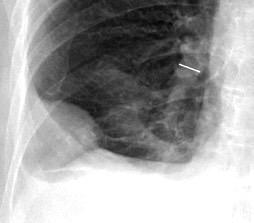

Neumonía a neumococos base izda. con derrame que aumenta.

Broncograma en lateral y en US.

(36-66% en ingresados)